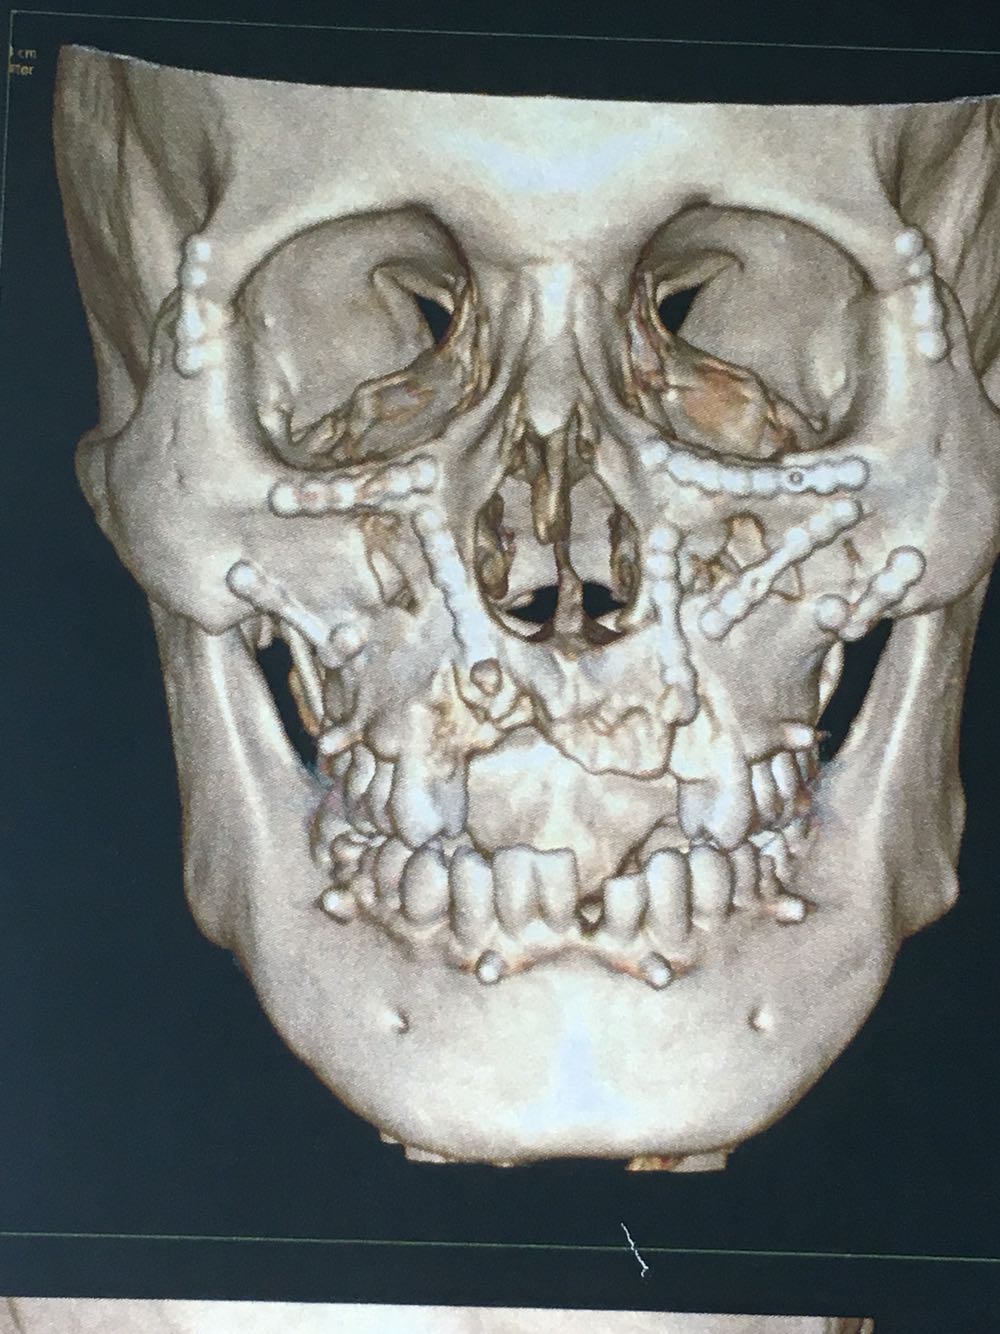

主诉:上颌骨骨折及锁骨骨折术后1年要求拆除内固定装置

治疗:全麻下双侧上颌骨骨折术后留置钛板取出及锁骨骨折术后钢板取出